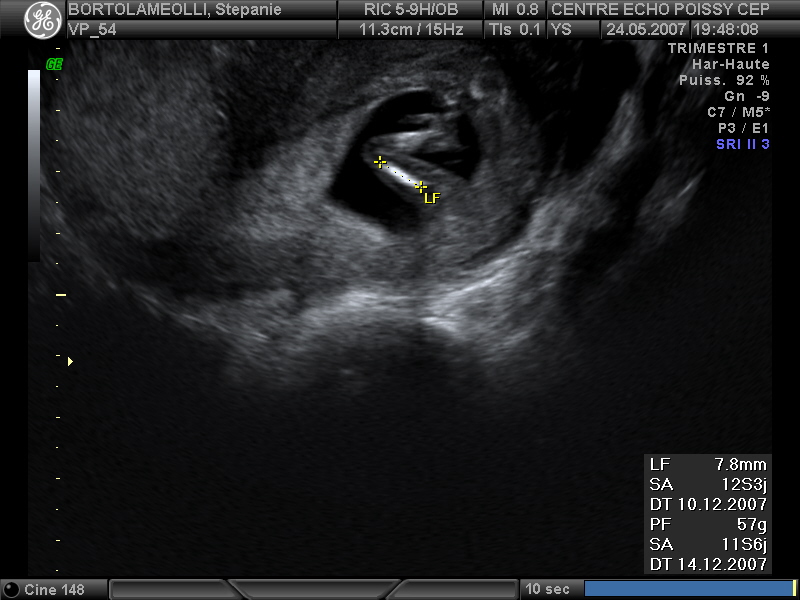

Echographies

Mai 2007